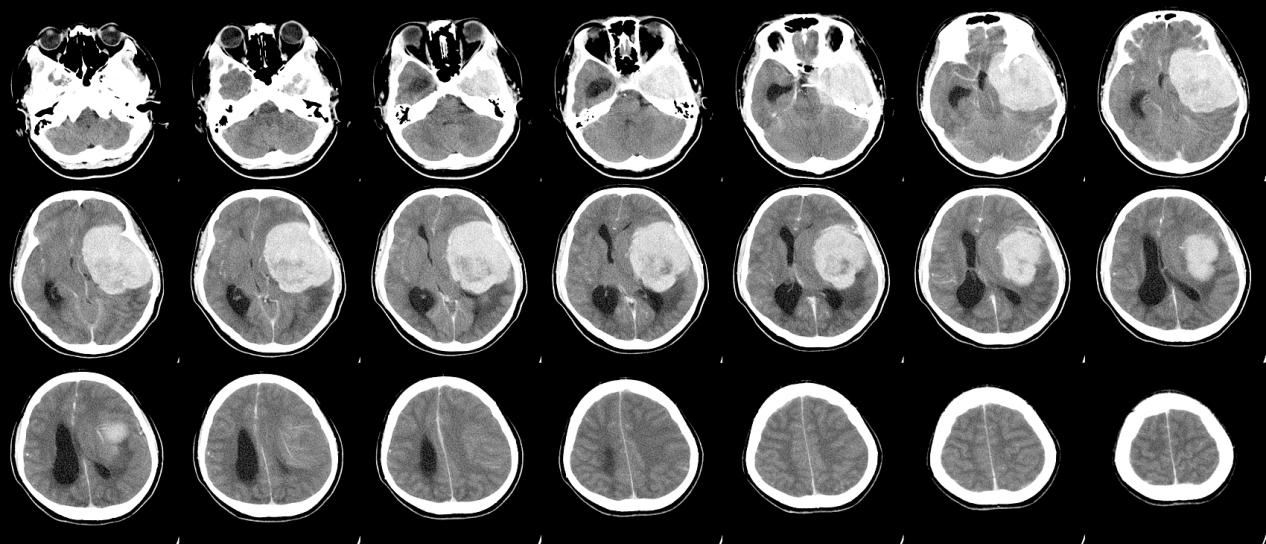

脑血管瘤晚期能活几年

脑血管瘤晚期存活率,昆明脑血管瘤去哪家医院-昆明医科肿瘤医院脑血管瘤是一种血管系统疾病,其发展和预后因多种因素而异。脑血管瘤的晚期通常指瘤体已经较大或出现严重的症状,并且可能存在其他合并症。在这种情况下,预测患者的寿命变得更加困难,因为每个患者的情况都是独特的...

脑血管瘤的症状是什么和诊断方式有哪些

脑血管瘤的症状有哪些,昆明脑血管瘤医院哪家好-昆明医科肿瘤医院导言:脑血管瘤是一种常见的脑部血管系统疾病,它可以在任何年龄段出现,并可能导致严重的神经功能障碍。本文将介绍脑血管瘤的常见症状和诊断方法,以增进对这一疾病的认识和早期发现。一、脑血管瘤的症状:脑血管...

脑血管瘤的定义和分类有哪些

什么症状是脑血管瘤,昆明脑血管瘤医院哪家好-昆明医科肿瘤医院导言:脑血管瘤是指在脑部或脑膜血管系统内形成的良性肿瘤。它由异常的血管组织构成,可能会对脑功能产生不良影响,并有潜在的出血风险。脑血管瘤可根据其组织学类型、血管类型和生长方式进行分类。本文将介绍脑血管...